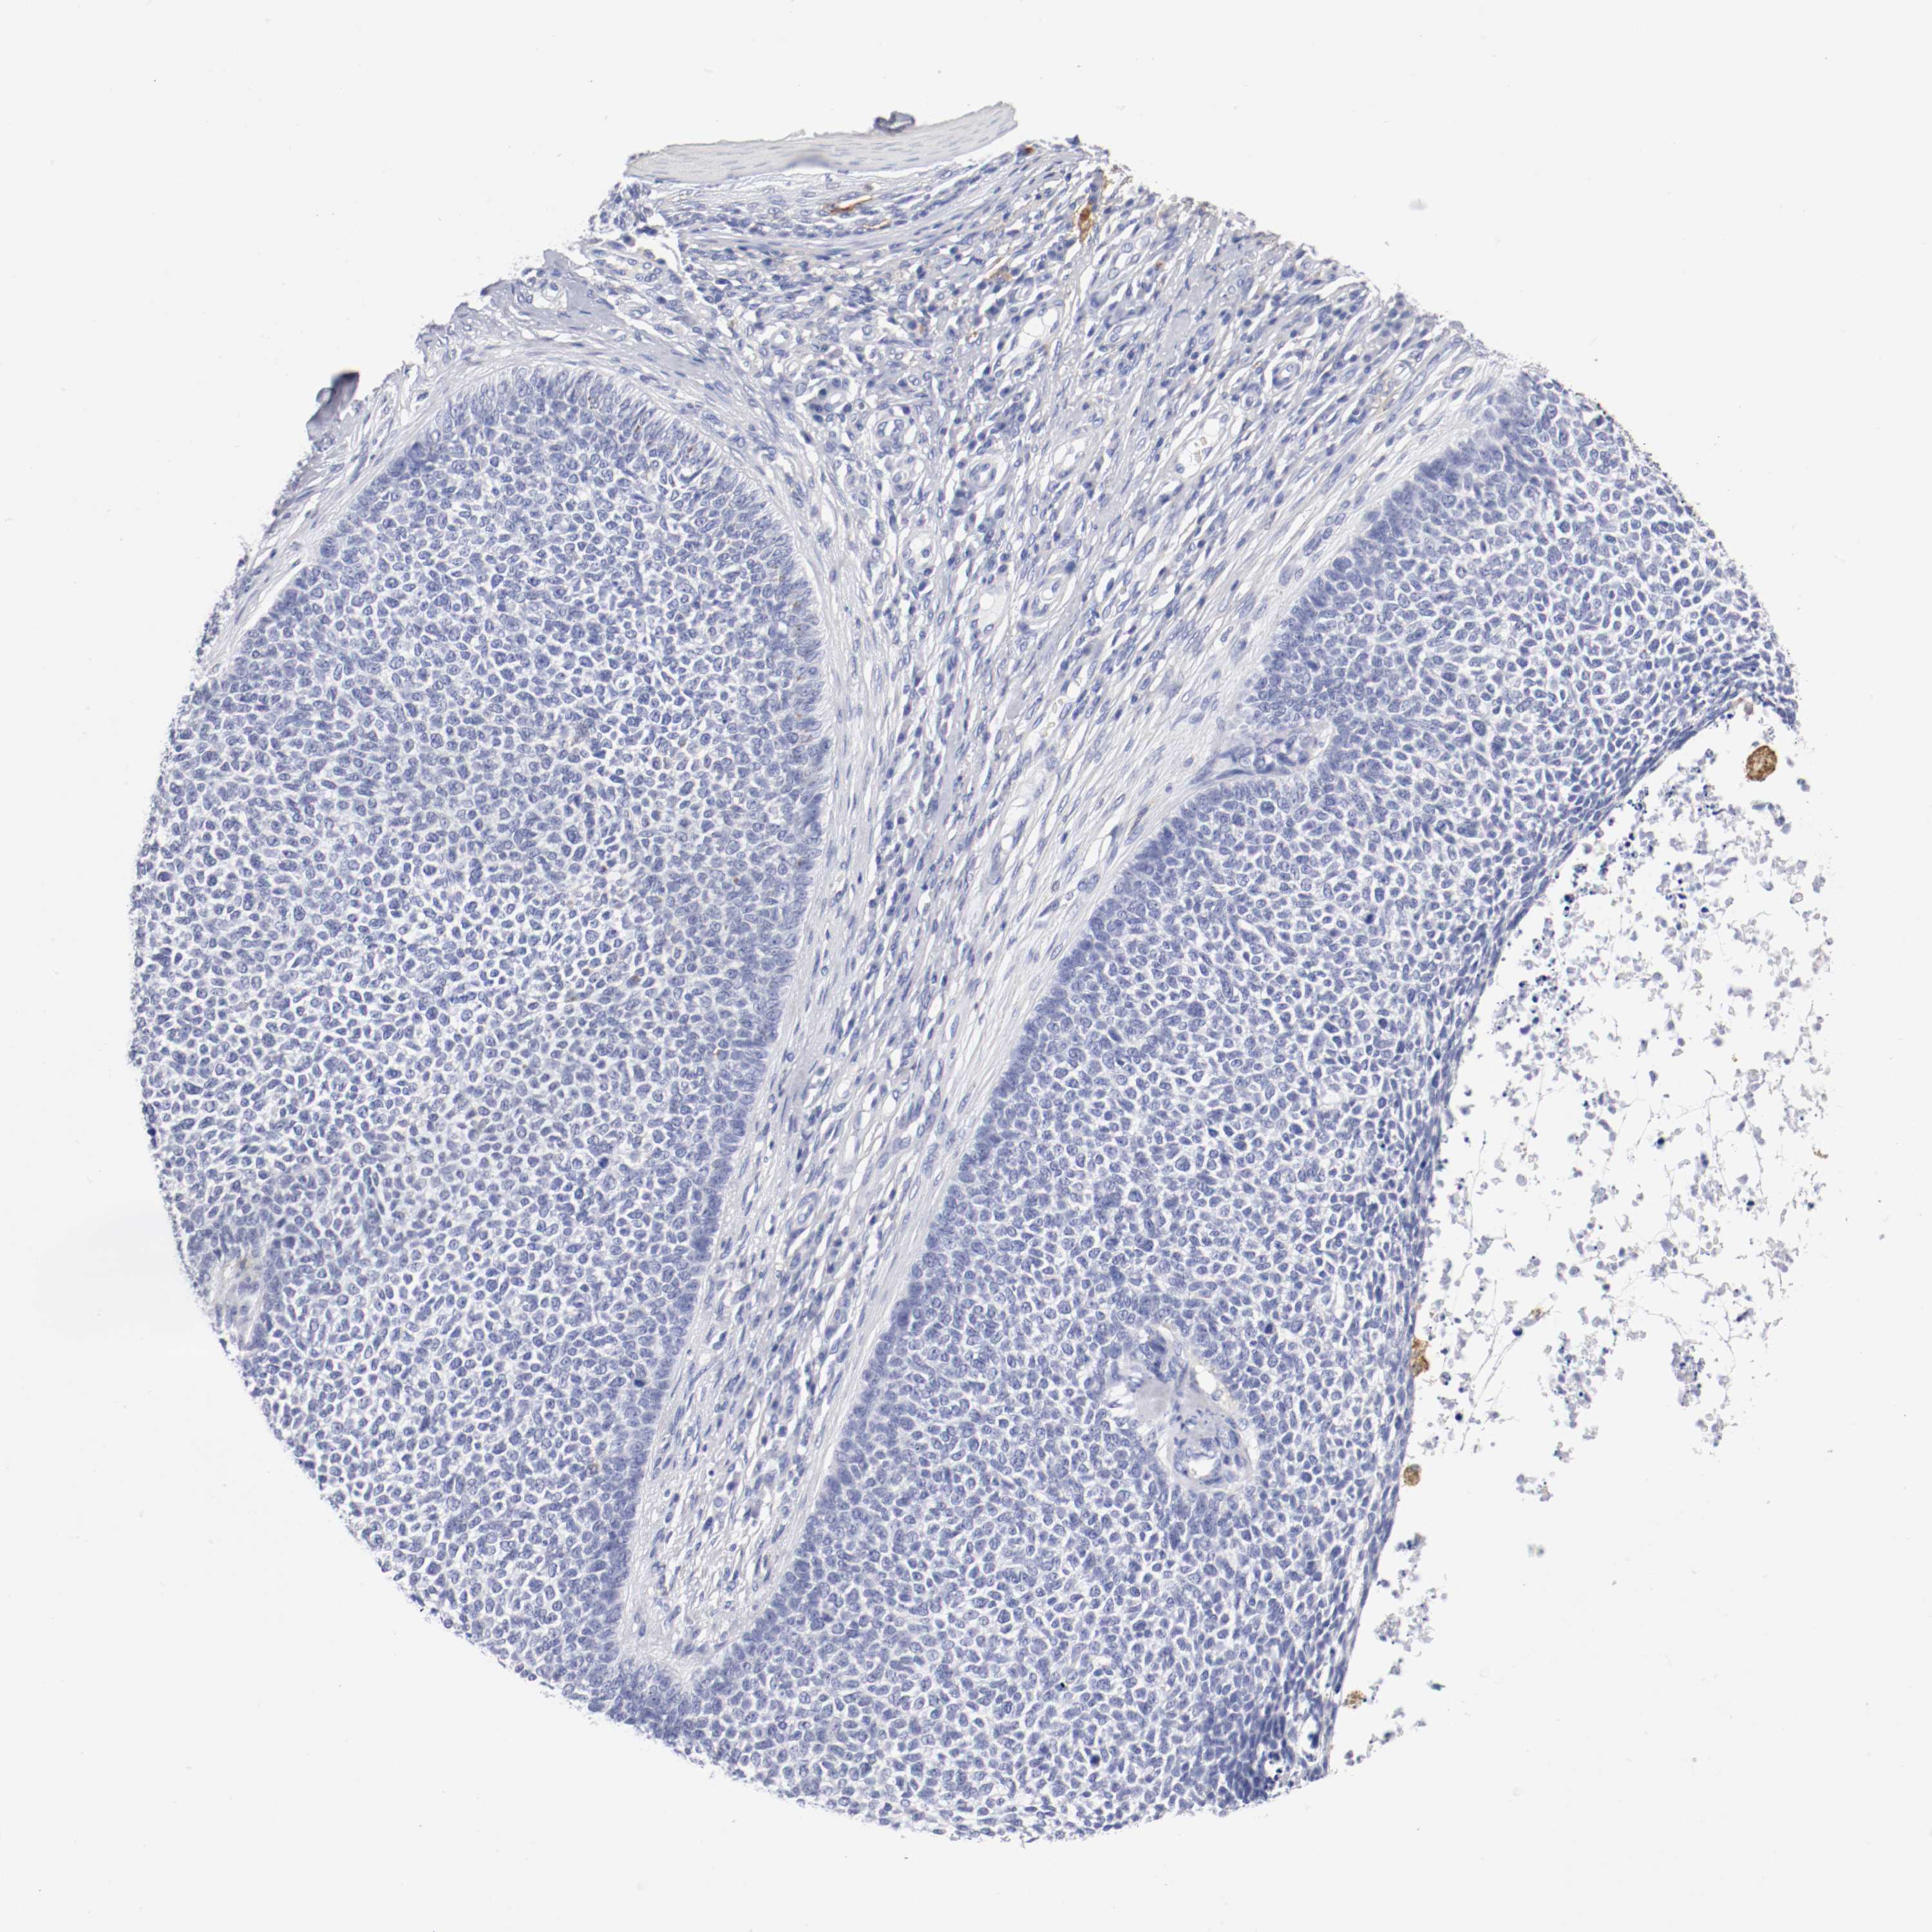

SKIN CANCER - Protein expressioni

A mouse-over function shows sample information and annotation data. Click on an image to view it in a full screen mode. Samples can be filtered based on level of antibody staining by selecting one or several of the following categories: high, medium, low and not detected. The assay and annotation is described here.

Antibody stainingi

Antibody staining in the annotated cell types in the current human tissue is reported as not detected, low, medium, or high, based on conventional immunohistochemistry profiling in selected tissues. This score is based on the combination of the staining intensity and fraction of stained cells.

Each image is clickable and will lead to virtual microscopy that enables deeper exploration of all samples and also displays staining intensity scores, fraction scores and subcellular localization as well as patient and tissue information for each sample.

Antibody CAB072871

Squamous cell carcinoma, NOS

Basal cell carcinoma